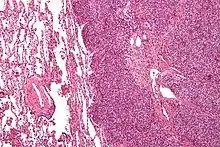

Histopathology

There are typically many small cells of the same size and appearance, with round nuclei.[3] Around half have extensive glycogen deposits, demonstrated with positive PAS staining.[3] Around 85% of Ewing sarcomas are positive for CD99, a cell-surface glycoprotein.[1] However, CD99 also occurs in some normal tissue and in other round cell sarcomas, as well as in lymphoblastic lymphoma and leukemia.[3] There may be keratin expression.[1]